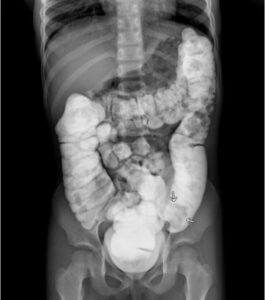

Colocolic Intussusception. Contrast Enema. JETem 2024